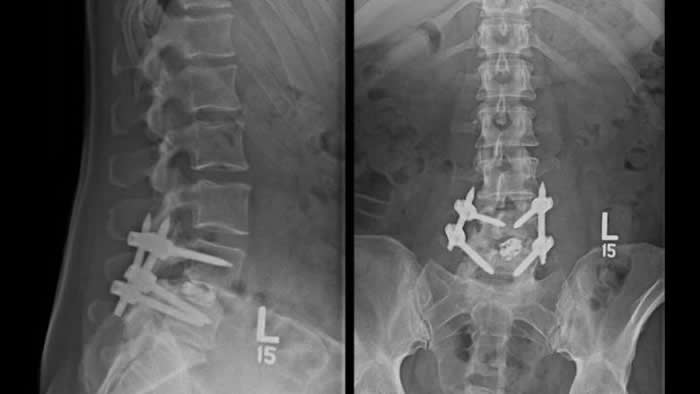

在对测试3种电刺激(一种为植入式,另外两种为穿戴式)的16项人体研究和17项动物研究进行回顾后,约翰�霍普金斯的研究人员现在确定,仅植入式直流电刺激装置可对动物和人体都能成功发挥作用。在融合过程中,将直流电刺激装置植入脊柱旁的皮肤下,并在六到九个月的恢复期内保持原位,然后取出。

使用植入式直流电刺激装置的患者的椎骨融合成功率是未使用装置患者的两倍多,而动物的融合成功率更高。尽管该植入式装置似乎对外科医师而言很有用,但植入后可能不能进行MRI检查,且其确实具有引起感染、不适和免疫反应的小风险。